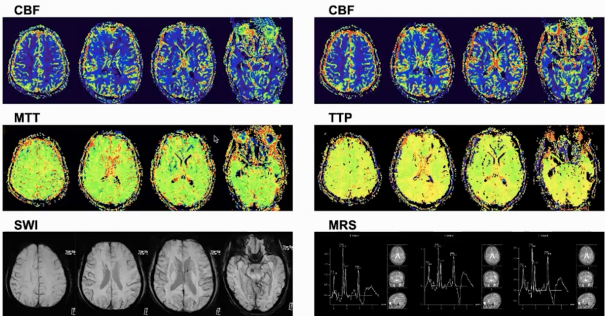

颅脑磁共振可见双侧额顶叶区域椎体束、胼胝体、右侧丘脑及脑干多发斑片状稍高信号,胼胝体压部异常信号影,Flair呈高信号,弥散轻度受限。增强扫描部分强化,灌注成像CBV、CBF稍增高,SWI未见明显出血及顺磁性沉着,MRS见Cho峰升高,NAA峰降低,局部Cho/NAA比值大于2,可见典型脂峰。

病灶累及范围深且相对对称,以双侧顶叶、额叶椎体束、前肢体、右侧丘脑、脑干等区域为主,部位和年龄与淋巴瘤相符,累及胼胝体膝部可见蝶翼征,增强扫描也符合淋巴瘤特征,但未见到典型的明显灌注减低,属不典型特征。